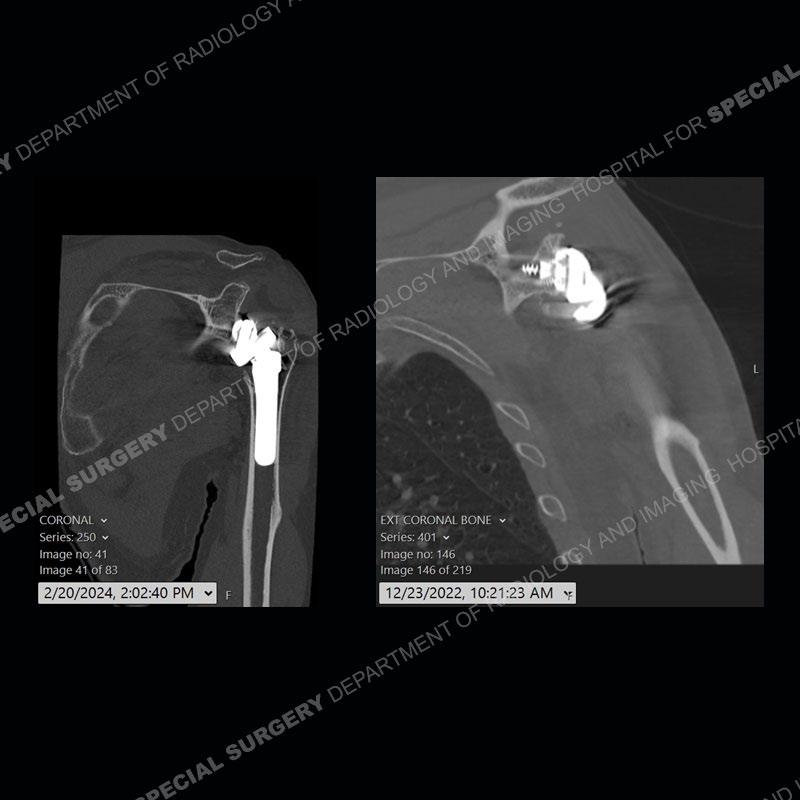

When comparing the radiographs, there is a slight change in the alignment in the components of the prosthesis. On the current radiographs, a radiolucent, crescentic focus is present at the level of the glenoid. When comparing the CT exams, there is a change at the alignment of the glenosphere and the humeral component and now a direct apposition of the components. On the current CT, the radiolucent, crescentic focus is again identified.

If comparison radiographs are present, subtle changes can be made more apparent. Instead of a space between the glenosphere and the humeral tray, there is a direct contact, and there may be an overall change in the alignment at the articulation. The displaced, radiolucent polyethylene liner depending on location can be seen on the radiographs, as in this case. At times, the liner may overlie other structures making identification very difficult on radiographs, but it should almost always be able to be identified on CT (as shown in this example as well). This patient is scheduled for revision procedure.